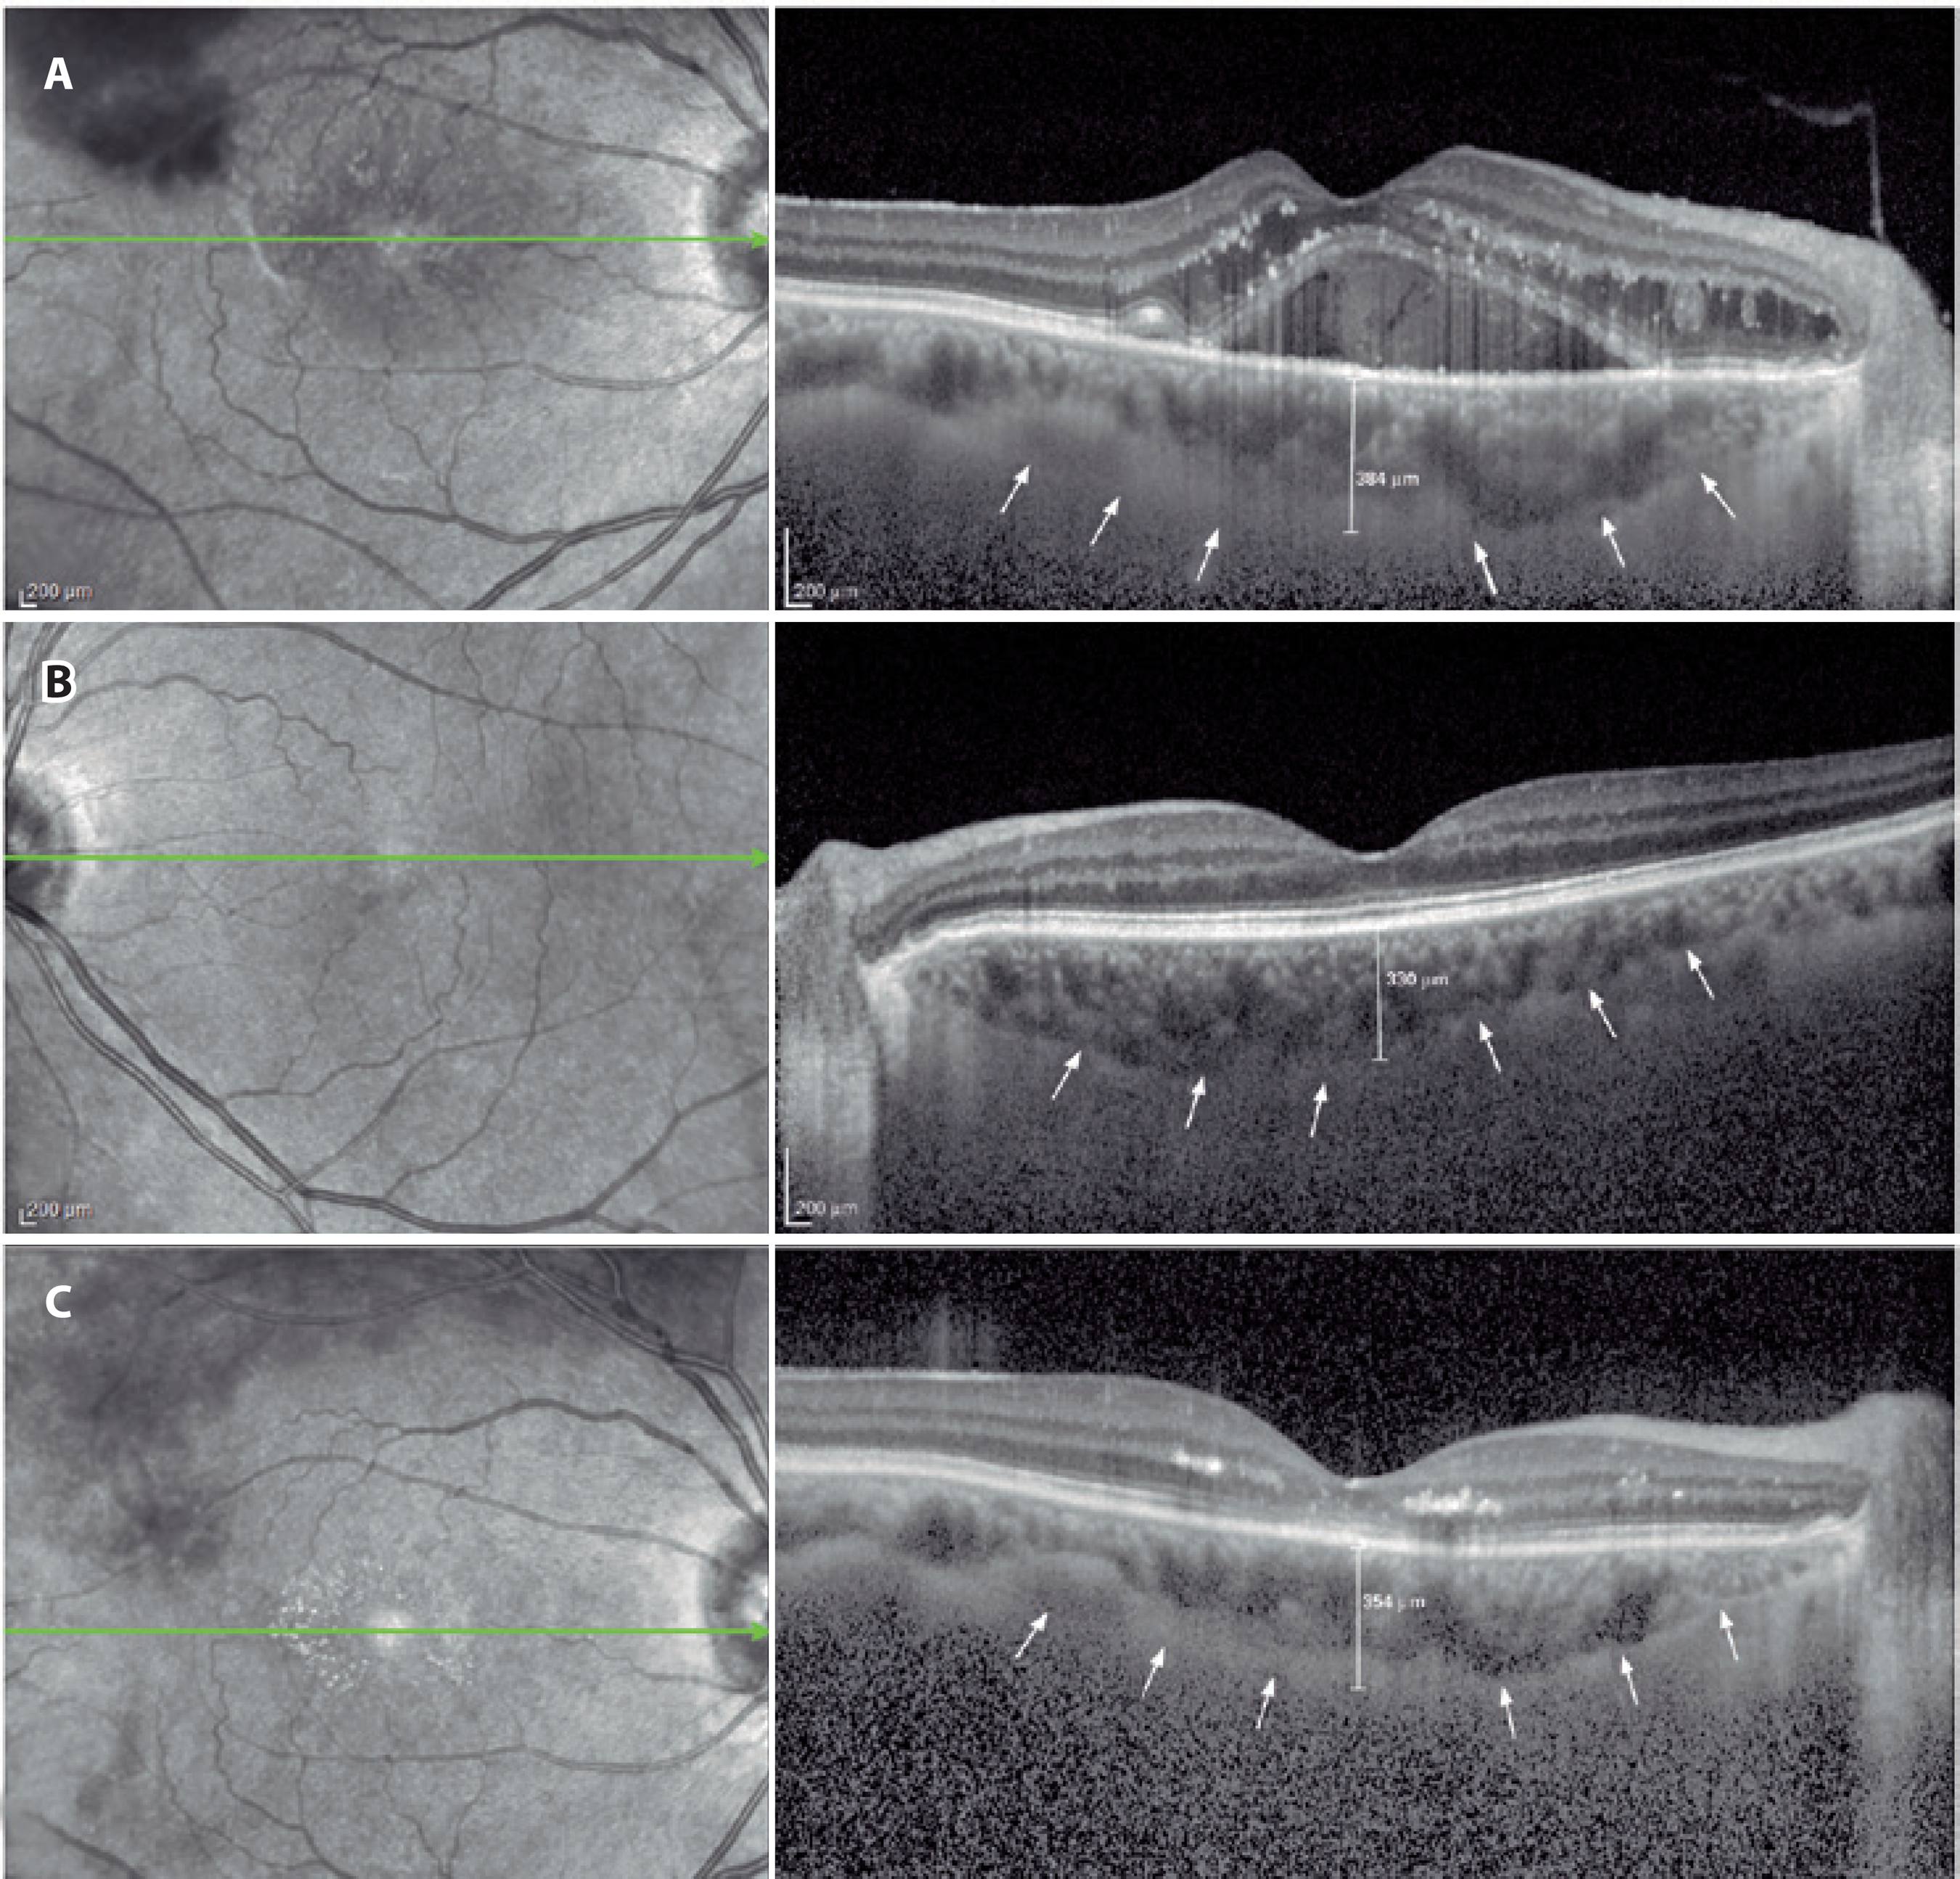

OCT measurements

Following detailed ophthalmologic examinations, a third-generation Spectralis OCT device (software version 5.6.3.0; Spectralis OCT, Heidelberg Engineering, Dossenheim, Germany) was used for ocular assessments. The method of obtaining EDI-OCT images has been previously reported(9,19). SFCT was determined as the vertical distance from the hyperreflective line of the hyperreflective retinal pigment epithelium to the line of the inner surface of the sclera centered on the fovea, which was taken using a tool with built-in linear measuring. A representative EDI-OCT choroidal image is presented in figure 1. Images were captured by one experienced clinician and assessed by another experienced clinician. Group identities remained anonymous to both clinicians.